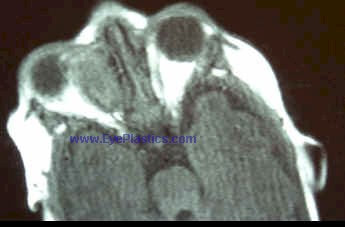

- CT scan detects an oval or round, homogenous mass with sharp margins, but falls short of a definitive diagnosis.

Imaging of Cavernous Hemangioma

- CT: smooth discrete lesion, fills with dye after 20 min; coronal cuts important to know tumor position relative to optic nerve. for sugical plan

- MRI: hypointense to fat on T1, hyperintense to fat on T2

- U/S: high reflectivity (A-scan high amplitude internal echoes)